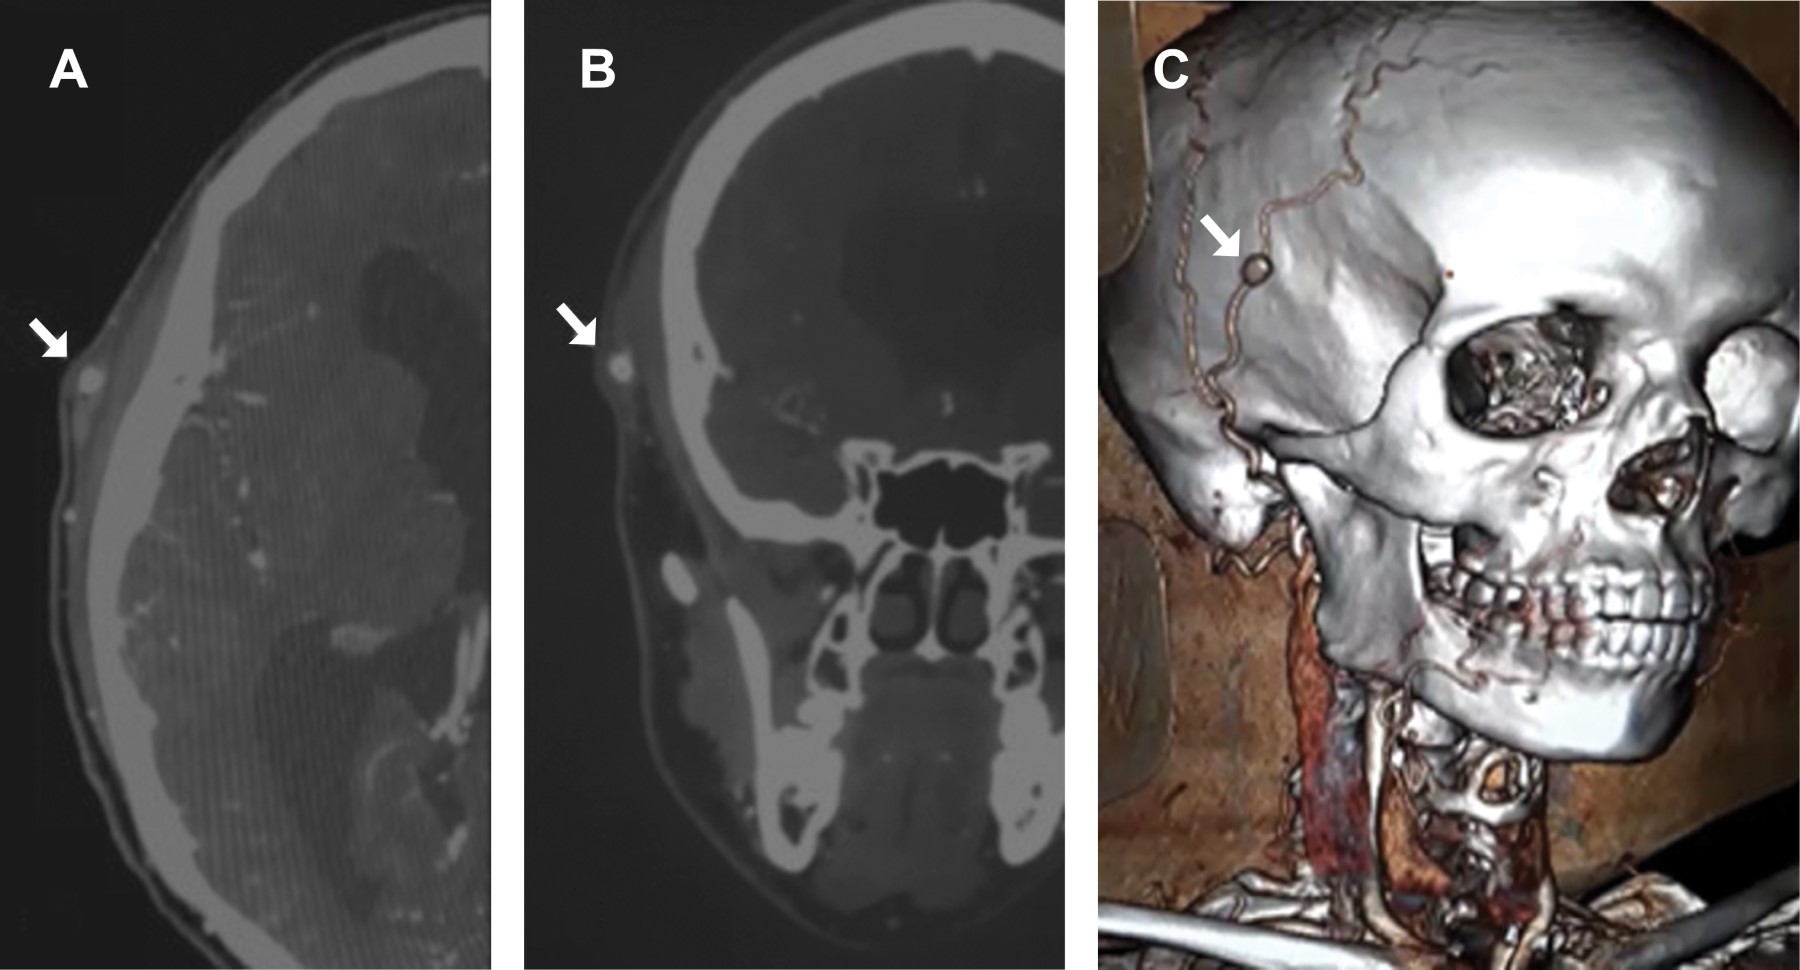

Posterior a ello se inicia protocolo diagnóstico, por lo que se solicita angiotomografía de cabeza y cuello con contraste intravenoso (Figura 2 A y B) y reconstrucción 3D (Figura 2C), en el que se visualiza disrupción de ATS derecha con paso de contraste a dicha disrupción, sin datos de fuga, por lo que se confirma como diagnóstico de PATS no roto.

Figura 2